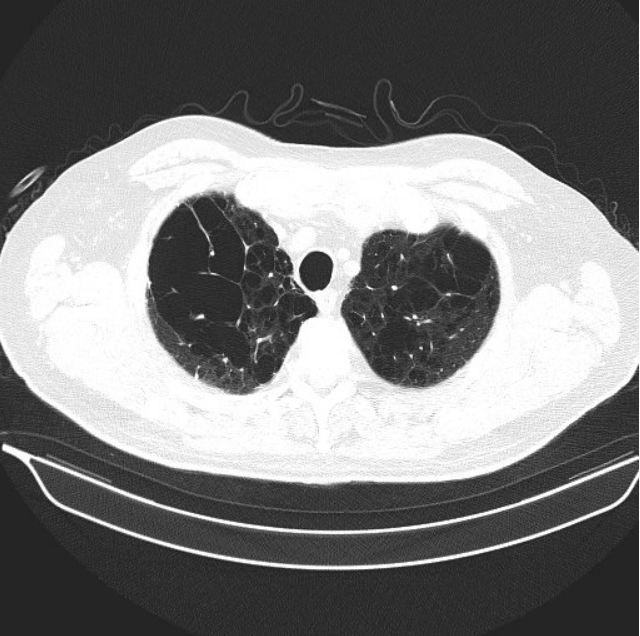

Figure 1.

The primary care physician was concerned about the possibility of interstitial lung disease or pulmonary malignancy. He sent the patient for a high resolution CT of the chest (Figures 1-3; please click figures to enlarge) as well as pulmonary function testing (Table, see next page).